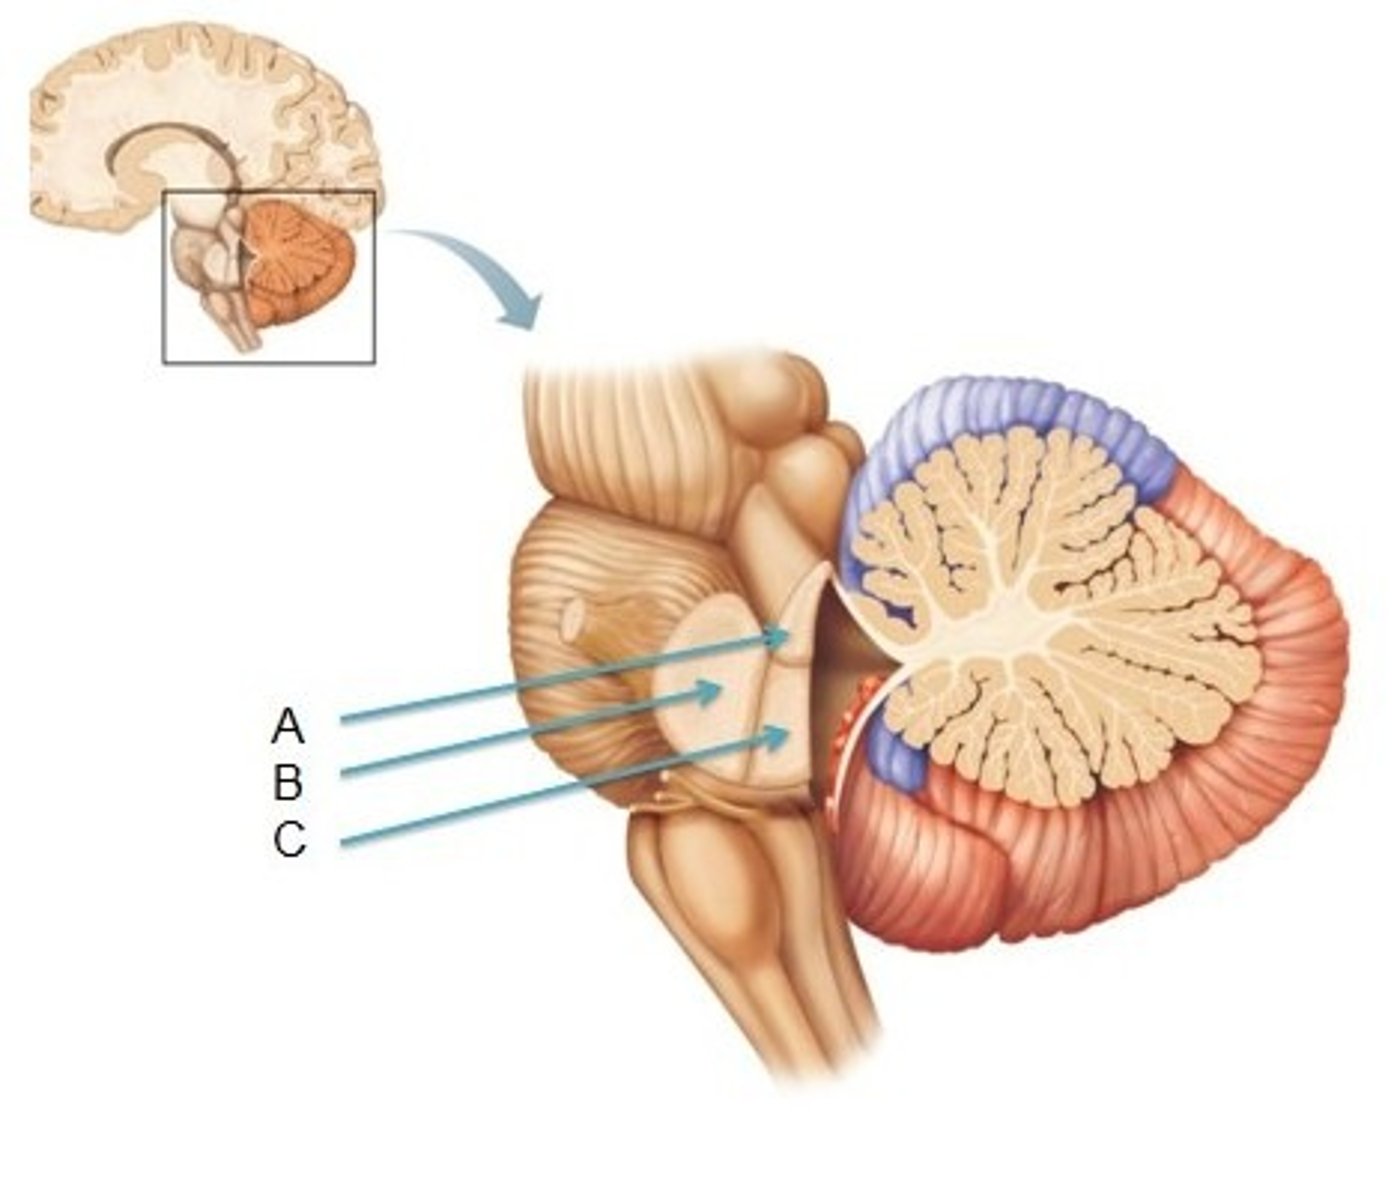

What is the superior boundary of the pons?

isthmus of the brain stem (between pons and cerebral peduncles)

What is the inferior boundary of the pons?

pontomedullary junction

refers to the large round protuberance on the ventral pons that represents a "bridge" of horizontally oriented fibers connecting the right and left sides

basilar portion

longitudinal midline groove of the pons that is the superior continuation of the ventral median sulcus/fissure, containing a namesake artery

basilar sulcus

white matter stalks that connect the pons to the cerebellum

middle cerebellar peduncles

What is the only cranial nerve that attaches to the pons?

CN V

portion of the pons that is dorsal to the basilar portion and represents mostly longitudinally oriented fibers and cranial nerve nuclei

**also helps to form the floor of the 4th ventricle

tegmentum

A

basilar portion

B

basilar sulcus

C

CN V

B

middle cerebellar peduncles

tegmentum

What forms the superior portion of the roof of the 4th ventricle? (A)

superior cerebellar peduncles

inverted V shaped interval between the superior cerebellar peduncles that is filled by a thin layer of white matter

superior medullary velum

lower portion of the roof of the 4th ventricle formed by a thin layer of pia mater and ependymal cells

inferior medullary velum

structure attached to the ventral surface of the inferior medullary velum in the 4th ventricle that helps form CSF

choroid plexus